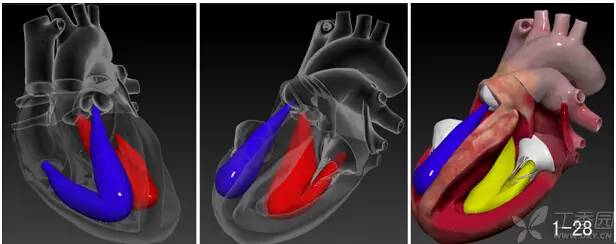

为了再次帮助亲们理解这一点,虫哥把右心室游离面透明化我们在正前方看心脏和室间隔应该是这个效果,类似的心脏的空间理念观会贯彻到随后的几个章节。

下面,我们挖开左室,看一看他的内部结构,左室和右室一样有流入道和流出道。注意一点,二尖瓣前叶是左室流入道和流出道天然的分隔屏障,这个不必用过于复杂语言去描述,大家还是感性认识一下(图 1-28)。